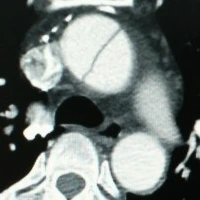

결국 고민하다 환자분께 설명하고 대동맥 조영 CT 를 확인하기로 했습니다. 환자도 통증이 변화하는 것이 좀 불안했는지 CT 촬영에 동의가 되었고 곧 확인한 대동맥 CT는……. 저명하게 상행 대동맥에 박리가 진행되고 있었습니다.

1.png

상행 대동맥 박리……. 머리로 가는 혈관을 막을 수 있고 심장 주위 심낭에 피가 차오르면 심장이 눌려 뛰지 못하는 심장압전(Cardiac tamponade)이 오면서 환자가 급사할 수 있는 초 응급 상황입니다. 하행 대동맥까지 박리가 진행되었다면 가슴 X-ray 사진에서 종격동 확장이 보였겠지만 이 환자의 경우와 같이 상행 대동맥에만 박리가 있으면 정말 알기가 어렵습니다.